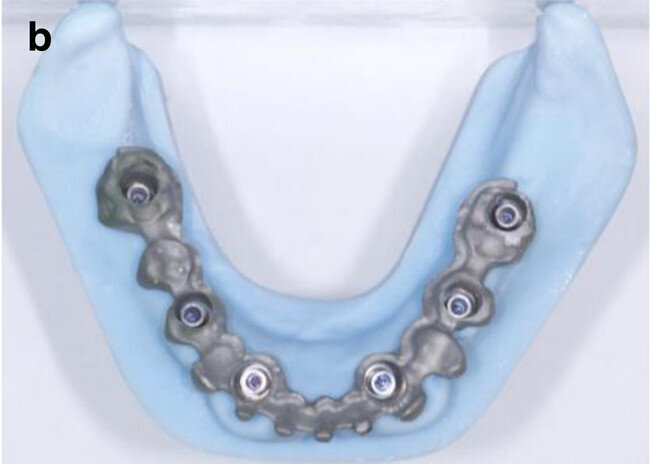

Fig. 5b: CAD/

CAM-fabricated surgical guides: tooth- and mucosa- supported (a) and implant- and mucosa-supported (b).

After extraction of the painful and extremely mobile teeth #41, 31 and 32 and adaptation of the existing RPD, a cone beam computed tomography scan (PaX-Uni3D, VATECH) with a 5 x 8 cm field of view, 85 kVp generator voltage, 5.5 mA generator current and 0.2 mm voxel size was performed to proceed with the detailed implant planning (Fig. 4). Based on the anatomical conditions and prosthetic planning (i.e. tooth set-up for the provisional RPD), six implants were virtually planned (3Diagnosys, 3DIEMME) in positions #46, 44, 42, 33, 35 and 36. As the implant positions #42 and 33 interfered with teeth #43 and 33, a two-step procedure with two surgical templates was planned for the guided implant placement (Figs. 5a & b). The templates were fabricated stereolithographically (DS3000 and XFAB, DWS) according to the virtual implant planning. Based on the same digital file (Figs. 6a–c), a provisional fixed dental prosthesis (FDP) was prepared preoperatively, allowing for an intra-oral adaptation between the abutments and the framework in order to achieve a passive fit (Figs. 7a–d).

The use of CAI software in the preoperative virtual 3D implant planning allowed for guided and immediate implant placement, and proved to be especially beneficial in the mandibular full-arch case presented. While there are some studies that have investigated outcomes of immediately loaded implants placed in edentulous patients using computer-aided, template-guided surgery to support an FDP,[25] only few case reports are available in the literature that describe the entire workflow, the patient’s state in detail and the usage of guided surgery templates with subsequent immediate loading.[3, 4] The considerably more complex combination of immediate implant placement and immediate loading required a high level of organisation between the implantologist and technician, minimising the required compliance of the patient. Pozzi et al. reported excellent results with CAD/CAM crossarch zirconia bridges on immediately loaded implants placed with computer-aided, template-guided surgery.[26] Several investigators have presented analyses of recent studies in this context, elaborating on the factors that influence accurate implant placement but also the comparable outcome of the restorations after guided implant placement.[15, 20, 21, 27–31] In the present case report, two CAD/CAM surgical templates were combined in this partially dentate patient, with extraction of teeth #42 and 33 and immediate implants performed in a sequenced order. The first scanner-based template was tooth- and mucosa-supported, enabling a higher template stability and thus more accurate guided osteotomies and implant placement. Four posterior implants were placed with this approach, allowing support of the second surgical template after extraction of teeth #42 and 33. The stability on these four points was high, as the implants in positions #42 and 33 showed a torque value of 35–40 Ncm each. The placement of the subsequent two anterior immediate implants was thus perfectly guided.